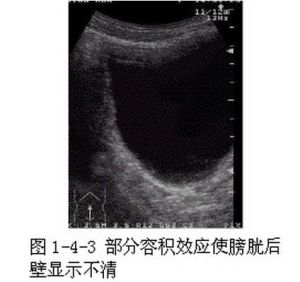

部分容積效應

部分容積效應由掃描解析度而決定的部分容積效應是一個關係重大的技術因素。大多數PET掃描的重建圖像解析度是5-10mm。然而這一數字還要受到重建前、重建過程中和重建後濾波的影響,以及重建和顯示採用的矩陣大小的影響。已有充分的證據說明,對小於2倍解析度的物體進行測量會導致各種各樣的、或許非常顯著的部分容積效應。而且,部分容積效應的校正往往是複雜和費力的。雖然如此,部分容積效應的校正對於標準攝取值法診斷準確性的提高作用已經得到證實。這一點至關重要,因為很多治療措施會縮小腫瘤的體積。如果沒有部分容積效應的校正,小腫瘤的 18F-FDG攝取可能會被低估。